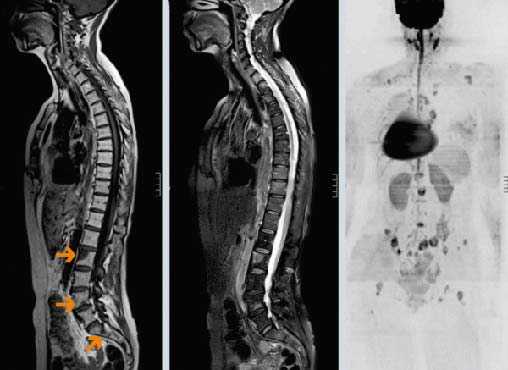

Стандартный протокол МРТ исследования позвоночника при подозрении на метастатическое поражение состоит из Т1-зависимых сагиттальных МРТ позвоночника и Т2-зависимых МРТ с подавлением сигнала от жира. Литические метастазы замещая костный мозг выглядят гипоинтенсивными на Т1-зависимых МРТ. На Т2-зависимых МРТ позвоночника они могут быть гипоинтенсивными, изоинтенсивными, если они склеротические, либо яркими, если они литические, особенно при подавлении сигнала от жира. Метастаз может диффузно поражать костный мозг позвонка или быть очаговым. На самой ранней стадии диффузного поражения заметно исчезновение сигнала при МРТ позвоночника от вертебробазилярной вены, процесс захватывает ножки дуг и задние структуры позвонка. Параспинальное распространение лучше видно на Т1-зависимых коронарных МРТ срезах, а компрессия спинного мозга на сагиттальных МРТ. На последнем этапе желательны контрастированные Т1-зависимые МРТ позвоночника в сагиттальной и поперечной плоскостях. Чувствительность МРТ превышает 90%, что заметно превосходит радионуклидную диагностику. В плане дифференциации метастазов и доброкачественных заболеваний МРТ не абсолютно надежна. Дифференциальная диагностика с гематологической патологией – плазмоцитомой, лимфомой и лейкозами практически невозможна и требует аспирационной биопсии. Реакцией костного мозга, напоминающей метастатическое поражение, сопровождаются доброкачественные переломы. Однако сигнал при МРТ позвоночника выражено неоднородный, задние структуры и костный мозг в заднем отделе тела позвонка остаются интактными. Более надёжным в плане дифференциальной диагностики является использование диффузионно-взвешенных МРТ. При доброкачественном переломе через 1 – 3 месяца сигнал возвращается к норме.

МРТ позвоночника. Сагиттальная Т1-зависимая МРТ. Множественные метастазы в позвоночник.

МРТ позвоночника. Сагиттальная Т2-зависимая МРТ. Множественные метастазы в позвоночник.

(Слева) Сагиттальный срез, Т1-ВИ, пациент с раком легкого: после проведенной лучевой терапии отмечается рецидив опухолевого роста. На уровне L2-L5 отмечается диффузное снижение интенсивности сигнала, на уровне L4-эпидуральное распространение опухоли.

(Справа) Сагиттальный срез, Т1-ВИ с КУ: множественные низкоинтенсивные метастатические очаги поражения, которые на фоне введения контраста становятся менее заметными вследствие диффузного усиления сигнала опухолью и приближения его интенсивности к сигналу жирового костного мозга.